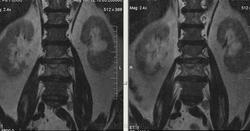

Метастазы рака простаты, кроме измений в позвонках видна сама первичная опухоль и лимфатические узлы (общий и наружный подвздошные слева, ещё один в левой подвздошной ямке).

После добавления томограмм исследования органов малого таза картина стала ещё печальнее...

Да, запустил пациент. До этого были проблемы с мочеиспусканием, рези, болезненность. Лечился самостоятельно от простатита, отмечал временное улучшение.